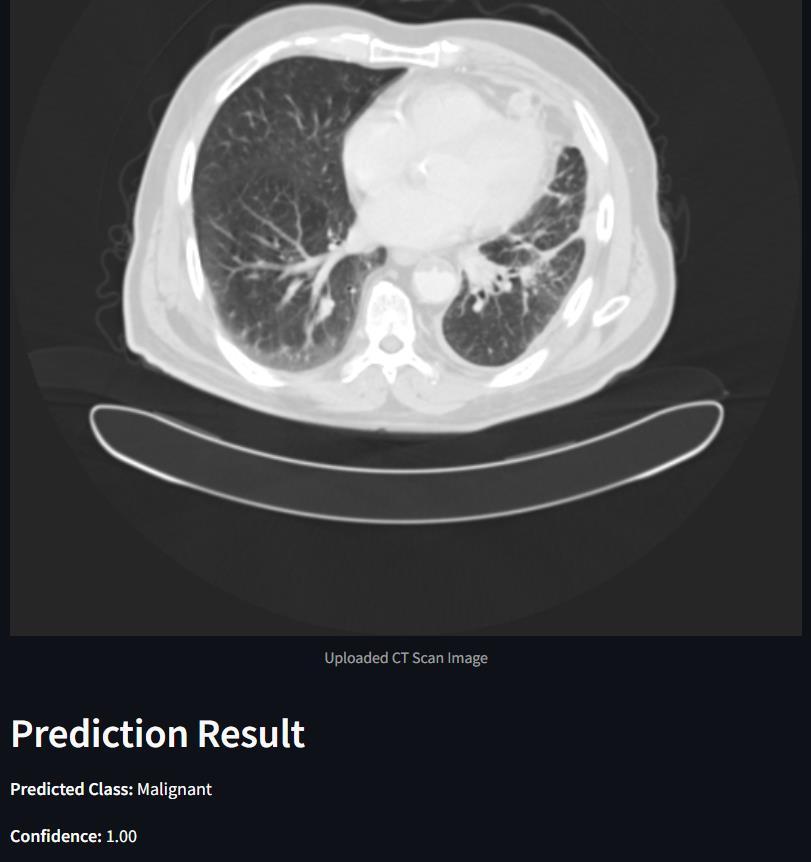

The final accuracy and performance metrics of the model are substantiated visually through a series of graphs and charts, showcasing accuracy and loss metrics across epochsforbothtrainingandtestingdatasets.Additionally, confusion matrices are created to represent classification performanceonbothtrainingandtestingdata,providinga clear and concise understanding of the model's behavior. Complementing these metrics are tumor images displaying predicted classes alongside model confidence scores, offering valuable insights into the model's effectiveness and emotional impact. This comprehensive presentationnotonlyevaluatesefficacybutalsofacilitates furtherrefinementandoptimization,ultimatelyenhancing overallperformanceforend-users.

The VGG- 16 model's performance on the IQ- OTH/ NCCD lung cancer dataset is exhaustively presented through a collection of visual aids. These include graphs and charts depicting accuracy and loss metrics over epochs for both trainingandtestingdatasets.Likewise,confusionmatrices are generated to illustrate the classification performance of the model on both training and testing data. This detailed representation offers precious perceptivity into the behavior and efficacy of the VGG- 16 model on the specifieddataset.

Output: